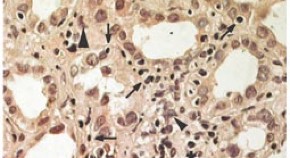

• Membranous nephropathy is an uncommon form of lupus nephritis, accounting for only one-fifth of all cases. As a result, few reviews have focused on this condition. Here, Chi Chiu Mok summarizes the histological classification, clinical presentation, outcomes and therapy of membranous lupus nephropathy. As the optimal therapy for this form of lupus nephritis remains unclear, the author provides an algorithm to help guide treatment.